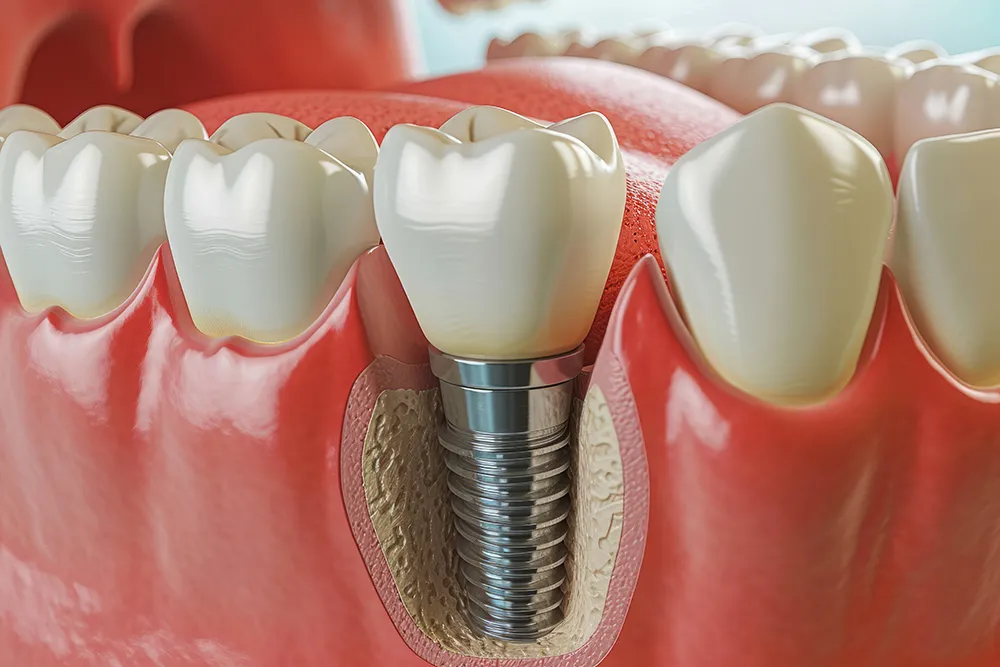

전체 임플란트는 위아래 각각 14개씩 28개의 치아가 있으며 14개의 치아 모두 상실된 경우 14개의 임플란트를 모두 식립하는 것이 아니라 8~10개의 임플란트를 식립 후 머리 부분의 치아를 연결하는 방식입니다.

즉, 여러 개의 인공 치아 뿌리(임플란트)를 잇몸과 턱뼈에 식립하여, 그 위에 고정식 틀니나 브릿지를 장착하는 치과 치료 방법입니다. 이는 주로 전체 치아가 상실된 환자들에게 적용되며, 부분적인 치아 상실을 보완하는 부분 임플란트와 구분됩니다.

전체 임플란트는 기존의 틀니와 달리, 잇몸에 직접 고정되어 있어 안정성과 편안함이 뛰어납니다. 또한, 자연치아와 유사한 힘을 발휘할 수 있어 음식 섭취나 발음 등 일상적인 활동에서도 큰 불편이 없습니다. 이러한 특성 덕분에 많은 환자들이 전체 임플란트를 선택하고 있으며, 치과계에서도 적극 추천하는 치료법 중 하나로 자리 잡고 있습니다.